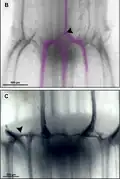

- Haz colateral cerrado. En la mayoría de las pteridófitas, monocotiledóneas y dicotiledóneas herbáceas, los haces vasculares no conservan procámbium después que los tejidos vasculares primarios alcanzan el estado adulto. Carecen por lo tanto de capacidad para un crecimiento ulterior. Los elementos traqueales del protoxilema eventualmente se estiran y destruyen. En los haces vasculares de muchas poáceas (gramíneas) la destrucción del protoxilema lleva a la formación de un espacio abierto llamado laguna protoxilemática.